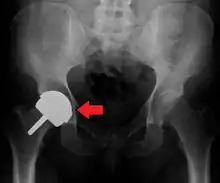

Configuration

Post-operative projectional radiography is routinely performed to ensure proper configuration of hip prostheses.

The direction of the acetabular cup influences the range of motion of the leg, and also affects the risk of dislocation.[9] For this purpose, the acetabular inclination and the acetabular anteversion are measurements of cup angulation in the coronal plane and the sagittal plane, respectively.

Acetabular anteversion.[81] This parameter is calculated on a lateral radiograph as the angle between the transverse plane and a line going through the (anterior and posterior) margins of the acetabular cup.[81]

Acetabular anteversion is normally between 5 and 25°.[9] An anteversion below or above this range increases the risk of dislocation.[9] There is an intra-individual variability in this method because the pelvis may be tilted in various degrees in relation to the transverse plane.[9]

Center of rotation: The horizontal center of rotation is calculated as the distance between the acetabular teardrop and the center of the head (or caput) of the prosthesis and/or the native femoral head on the contralateral side.[80] The vertical center of rotation instead uses the transischial line for reference.[80] The parameter should be equal on both sides.[80]